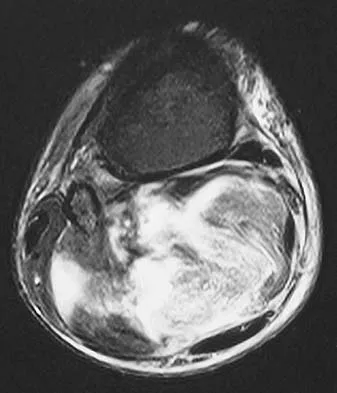

Question 67 High Yield

A 32-year-old laborer reports left ankle pain and deformity. History reveals that he sustained a left ankle fracture 2 years ago and was treated with closed reduction and casting. Radiographs are shown in Figures 25a through 25c. What is the most appropriate management?

Detailed Explanation

Corrective osteotomy of fibular malunions, with appropriate lengthening, even in the presence of early arthritis, has been shown to decrease ankle pain and increase stability. Reduction and bone grafting of the medial malleolar nonunion is also needed. There is no evidence supporting the use of intra-articular steroids or hyaluronic acid in the ankle joint. Lateral talar displacement of even 1 mm has been reproducibly shown to decrease tibiotalar contact by 40% to 42%, causing a predisposition to arthritis. Weber D, Friederich NF, Muller W: Lengthening osteotomy of the fibula for post-traumatic malunion: Indication, technique and results. Int Orthop 1998;22:149-152. Lloyd J, Elsayed S, Hariharan K, et al: Revisiting the concept of talar shift in ankle fractures. Foot Ankle Int 2006;27:793-796. Offierski CM, Graham JD, Hall JH, et al: Later revision of fibular malunion in ankle fractures. Clin Orthop Relat Res 1982;171:145-149.